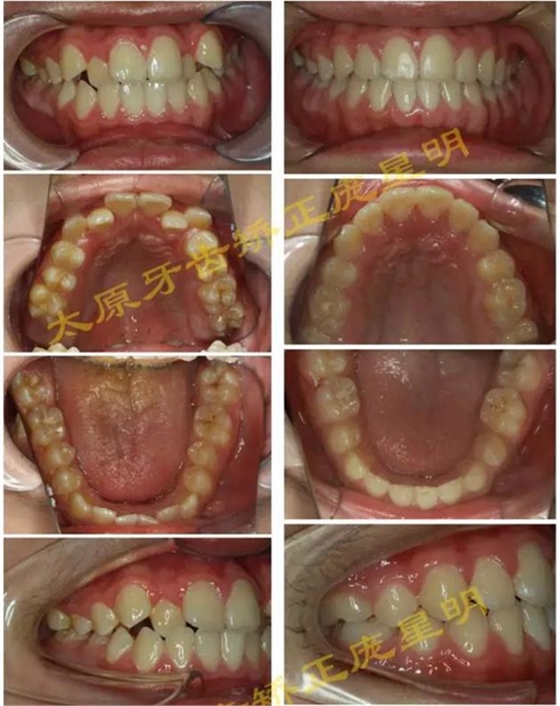

1500866161_694151.jpg1500866311_947305.jpg

此病例主要考慮的是垂直骨面型,矢狀骨面型,前牙覆合覆蓋及尖牙關(guān)系,側(cè)貌